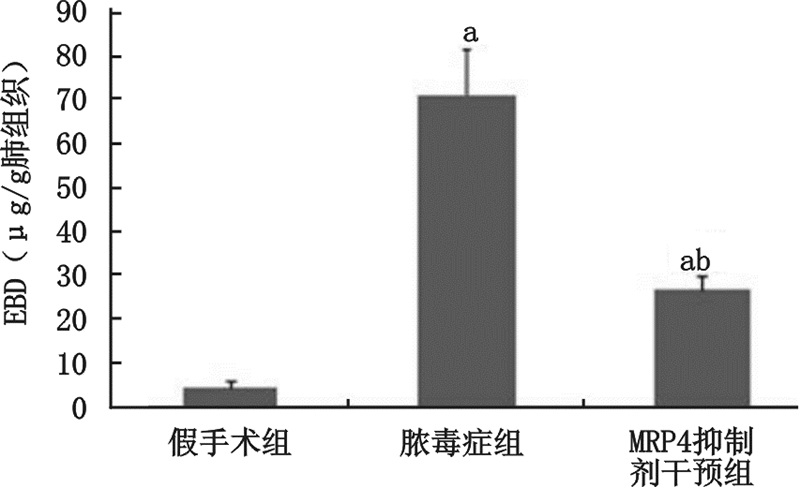

与假手术组大鼠相比,脓毒症组大鼠肺组织伊文思蓝含量显著增多,提示肺渗透性增强。与脓毒症大鼠组比较,MRP4抑制剂干预组大鼠肺组织伊文思蓝含量明显减少,提示肺渗透性降低。

1.5 伊文思蓝检测肺渗透性术后24 h麻醉大鼠后经左侧股静脉注射1%伊文思蓝液(EBD)(美国Amresco公司)2 mL/kg体质量,30 min后迅速行气管插管机械通气并经颈动脉放血处死大鼠,立即开胸剪开左心房,将连接输液装置的9号注射针头插入肺动脉圆锥,在2.94 kPa下用生理盐水灌流肺血管至左心房处为清亮液体为止。取部分右肺中叶(约100 mg),吸干表面水分及血液,称湿质量,将肺组织剪成约10 mm 3 小块浸泡于甲酰胺(美国Amresco公司)溶液中(每100 mg肺组织3 mL甲酰胺),置60 ℃恒温水浴中抽提24 h,待组织中色素全部浸出,取出组织,离心,取上清液,在与标准曲线相同的条件下,用酶标仪(美国Perkin Elmer公司)在630 nm波长处进行测定吸光度(A)值,在标准曲线上查出伊文思蓝含量,以每克肺组织中EBD含量反映肺血管通透性变化。

MRP4,又称ABC转运蛋白家族4(ATP-binding cassette transporter family class C4,ABCC4),是多药耐药蛋白大家族MRPs的一员。MRP4在肝脏、肾脏、脑、血管、上皮、平滑肌等多种组织存在高表达,主要参与转运细胞cAMP等内源性分子,调控细胞内的环核苷酸水平。研究发现,抑制MRP4 或基因沉默MRP4 可提高细胞内cAMP水平[16, 17, 18]。MRP4 降低细胞内cAMP 水平的机制之一为刺激细胞内前列腺素释放,降低细胞内前列腺素聚集,促进细胞内cAMP 外流[19]。研究显示,应用MRP4 抑制剂MK571可通过提高细胞内cAMP水平而有效阻止肺动脉高压、阿司匹林抵抗等疾病发生[20]。Leite 等[21]在酵母聚糖诱导的腹膜炎小鼠动物模型上研究发现,MRP4 抑制剂MK571 可显著降低血管渗透性、细胞迁移、组织水肿和炎性渗出。本实验采用经典的盲肠结扎穿刺来建立脓毒症大鼠动物模型,发现抑制MRP4可显著降低脓毒症大鼠血清促炎性因子水平,减轻肺组织损伤程度和炎性浸润,降低肺组织渗透性,提示抑制MRP4可显著改善脓毒症大鼠肺血管内皮屏障功能障碍。